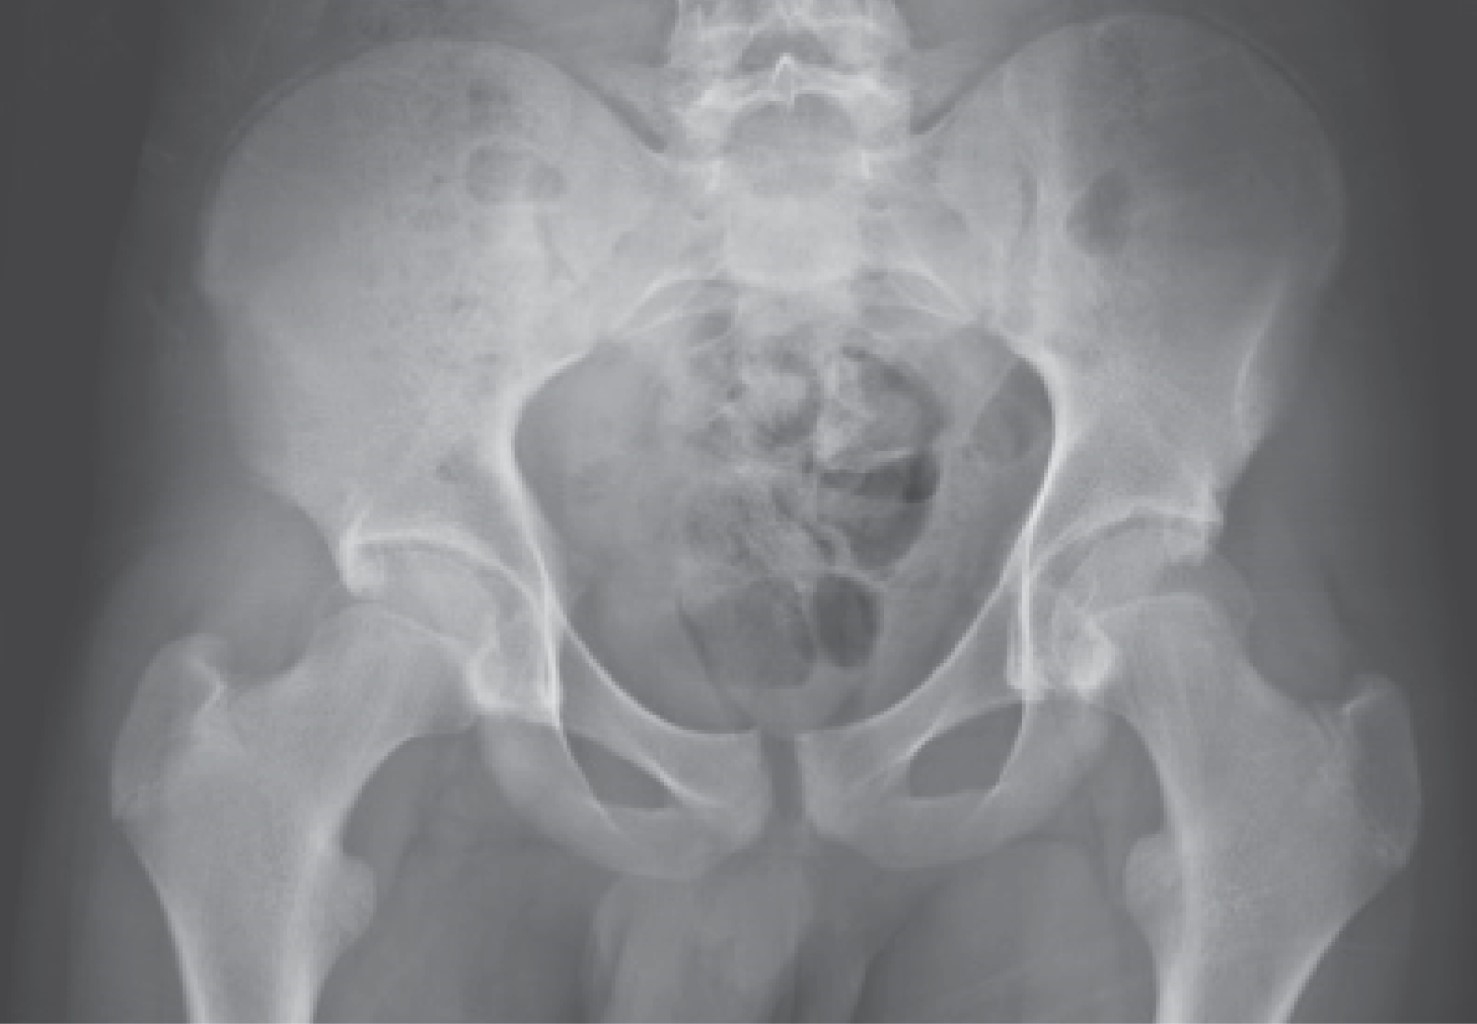

Tropical pyomyositis of the iliacus, obturator internus, piriformis and psoas major muscles in an immunocompetent patient with claudication

Sánchez-Rodríguez H, Morales-Ávalos R, Rivera-Zarazúa S, Ramírez-Elizondo M, Hernández-Rodríguez P, Vílchez-Cavazos F, Peña-Martínez V

Introduction: Pyomyositis is a term that denotes pyogenic infection usually primary skeletal muscle, associated with hematogenous dispersion due to transient bacteremia, or penetrating trauma, usually forming abscesses. Classically described frequently in tropical areas and predominantly affecting the lower limb musculature, however, in recent decades it has increasingly been associated with areas of temperate climates and relatively more frequently in immunosuppressed patients, being the patients under 30 years the most affected. Clinical case: Male of 15 years without relevant medical history. The patient had no history of trauma, falls, surgical interventions, infections or any other systemic condition. He came because of a clinical picture of 7 days of evolution characterized by pain referred to the groin and left iliac crest area associated with claudication and hyperthermia not quantified, which yielded partially to NSAIDs and paracetamol, but without achieving improvement so it is taken emergency by relatives. Conclusions: It is necessary to bear in mind this pathology when performing the differential diagnostic approach of a patient presenting with pain and functional limitation of some joint associated with data suggestive of an infectious or inflammatory process.

Figure 2